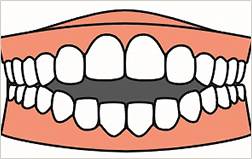

前歯が出ている

下の歯が上の歯より

でている

すき間が空いている

歯ががたがたする

噛み合わせが悪い

口を閉じても

閉まらない